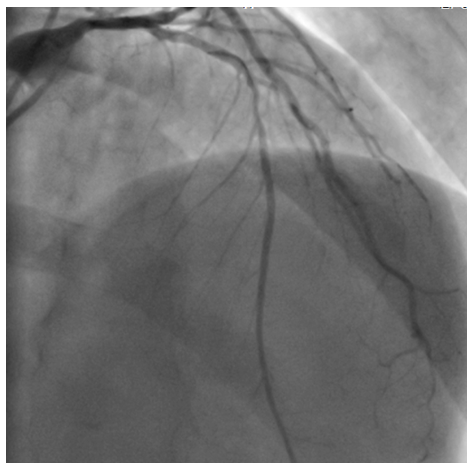

The second case

A 59-year old male, smoker, was admitted for anterior AMI with a cardiogenic shock in 2002. A primary PCI was done. In the angiogram, there was an acute thrombotic occlusion of the first segment of the LAD. A direct stenting of the culprit lesion was done successfully with a BMS (3.5/9mm; Synchro; SORIN®; Costa Mesa, California). No post-dilatation was done. Afterwards, he was discharged on ASA (100 mg once daily) and ticlopidine (500mg once daily for one month). Eleven years later, he was admitted again for chest pain due to an anterior AMI. Emergency coronary angiography revealed a total thrombotic occlusion of the stent of the LAD. On the IC stent®, there wasn’t an underdeployment. A predilatation with a balloon 2.5x15mm restored a TIMI III flow, then optimized by a non compliant balloon dilatation 3x8mm with an excellent angiographic result. He was discharged with DAPT (clopidogrel 75mg + ASA 100mg) for 3months then 100mg ASA daily alone long life. He was seen 3months later, free of any symptoms (Figure 4-6).

Figure 4 Thrombotic occlusion of the proximal LAD.